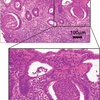

原発性硬化性胆管炎(PSC)

ひとこと:PSC、これは胆管の狭窄を認め、病変は肉眼サイズで確認可能! 大してPBCは肝内のちっちゃい胆管が病変になるので、「あ!胆道の狭窄がわかる画像だ!」って思ったのならそれはPSCなことが多い!